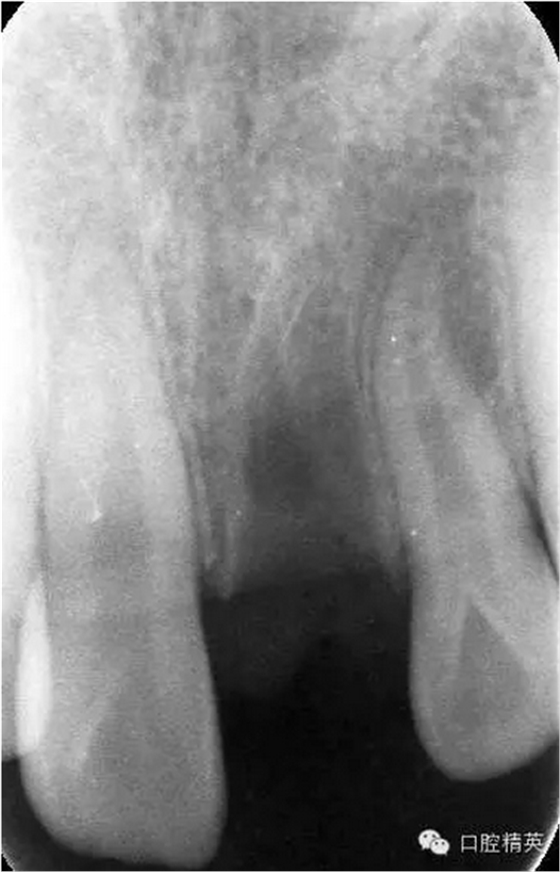

x線檢查:21牙槽窩空虛,窩內(nèi)未見(jiàn)其他遺留物。

圖3.患者21根尖片,牙槽窩空虛,無(wú)變形。